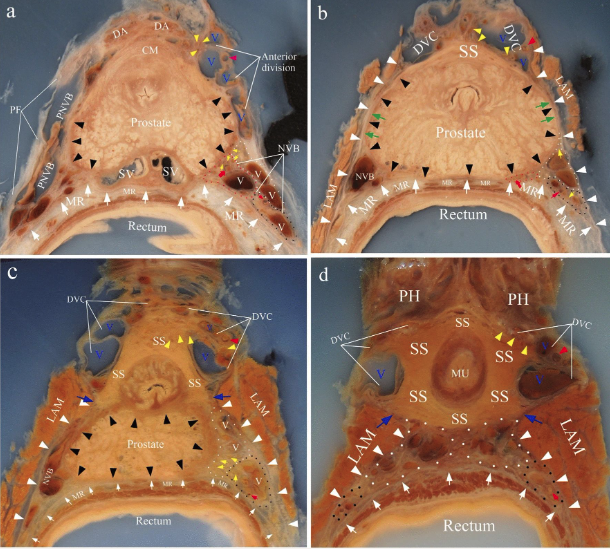

Dissection of the neovaginal canal is often the most difficult step of gender-affirming vaginoplasty due to the complex vasculature and surrounding structures.9 The ideal plane of dissection is between the ventral rectal fascia and Denonvillier’s fascia, which covers the dorsal surface of the prostate (Figure 2).10 In this area, the anterior rectal wall is supplied by the middle and inferior rectal arteries, which run posteroinferiorly between levator fascia and the fascia proper of the rectum. Neurovascular bundles supplying the prostate pass laterally in anterior (nerves, anterolateral pedicle of the prostatic artery, and veins) and posterior (deep artery, poster-lateral pedicle of the prostatic artery, and rectal arteries) divisions before joining the pudendal neurovascular bundle near the penile hilum. The distribution of vessels and nerves creates a safe area on the prostate’s dorsal surface. Understanding the vascular anatomy of this plane of dissection is critical. Damage to these vessels is responsible for major arterial bleeds and graft loss. Robotic assistance may improve visualization of these structures and allow for a more precise dissection. While robot assistance has been used in peritoneal flap vaginoplasty, its superiority in traditional penile inversion vaginoplasty for patients with adequate genital skin and tissue has not yet been evaluated. Advantages may include risk reduction of major complications and preserved sensory function; however, these must be weighed against the potential for additional time under anesthesia and the surgeon’s training.